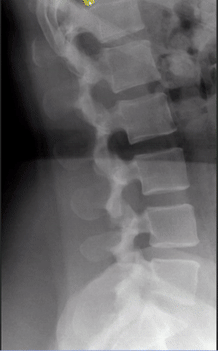

- Sagittal Spine Alignment

- Lumbar Curve